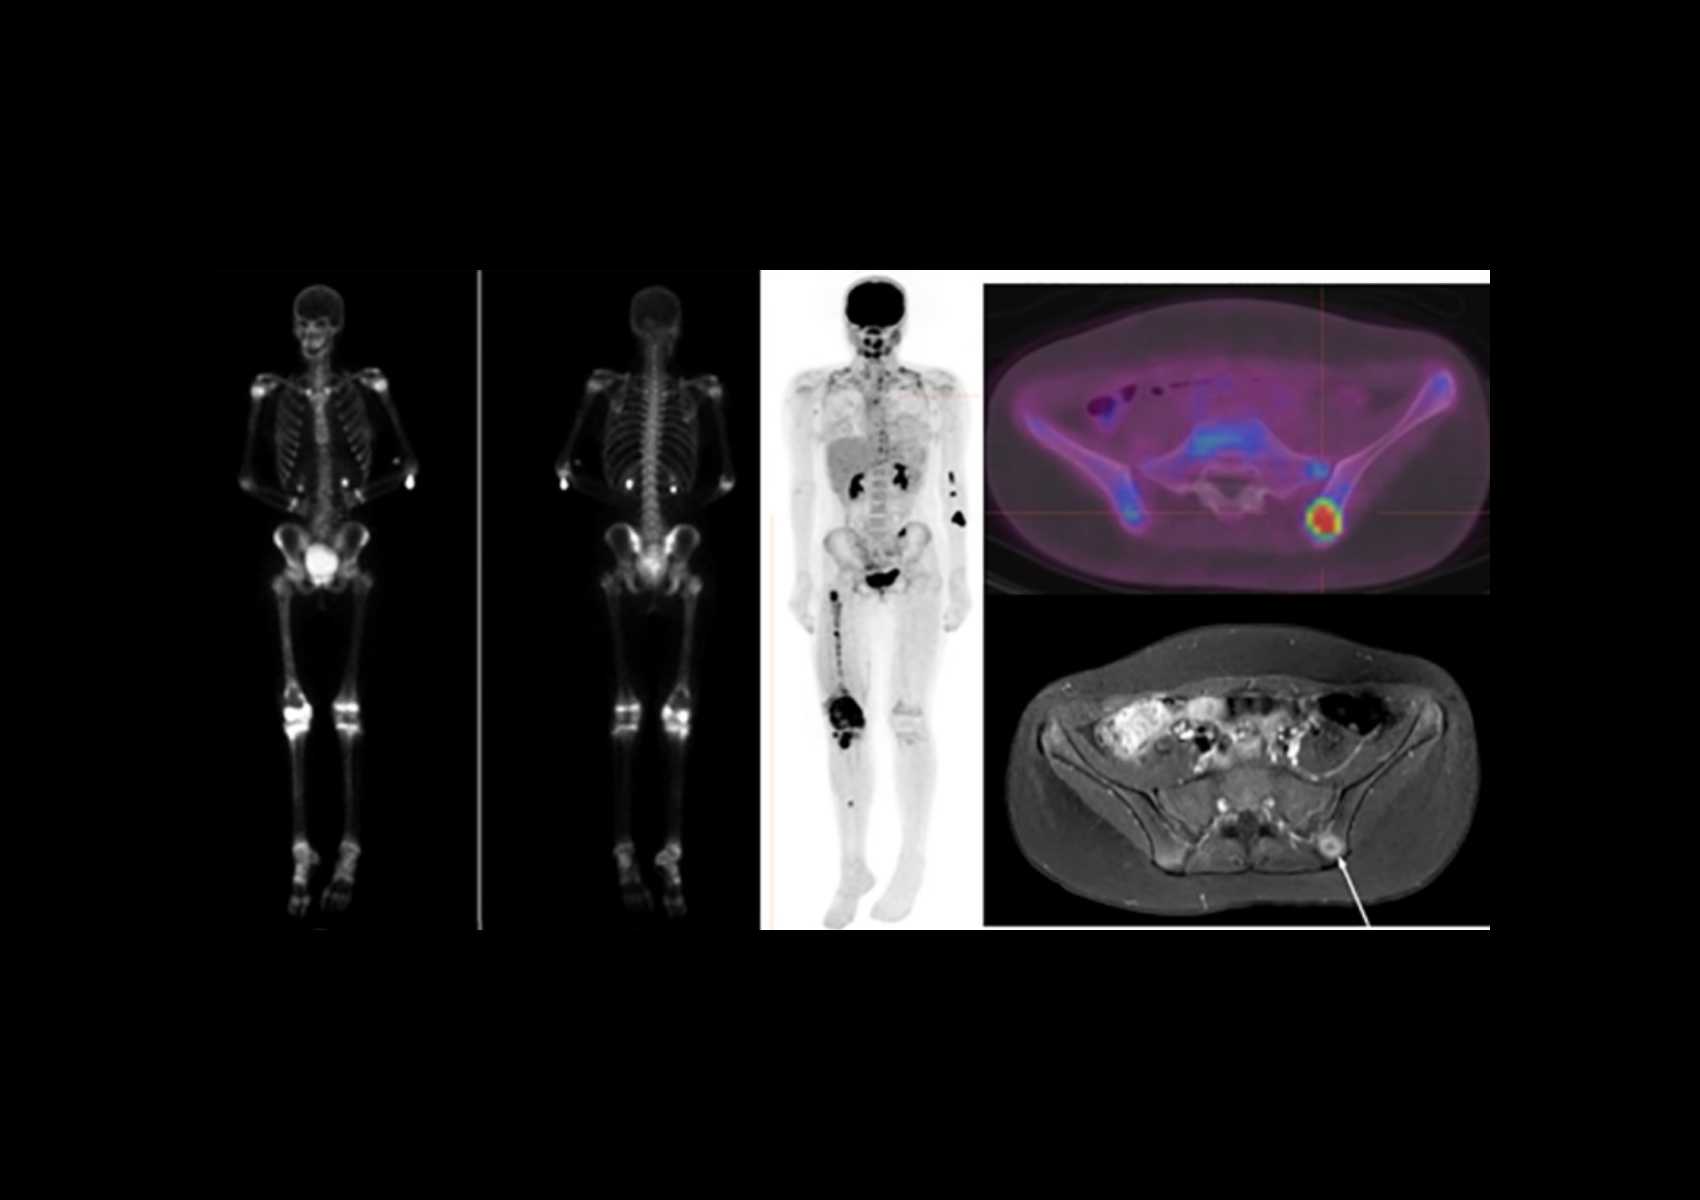

Moses Campus, along with Children’s Hospital at Montefiore Einstein, features 726 adult inpatient beds and 106 pediatric inpatient beds. The facility also offers services to outpatients. As an NCI-Designated Cancer Center, Moses provides diagnostic and therapeutic modalities through an active theranostics program. While training at Moses, residents partake in a particularly rigorous program in oncologic and non-oncologic pediatric and adult nuclear medicine. Our Transplant Center, also on-site, affords residents the ability to evaluate organ physiology pre- and post-transplant.